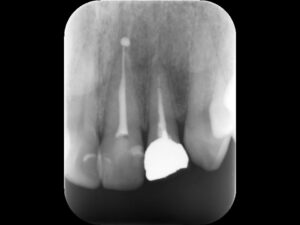

初診時レントゲン。他院にて根管治療を数か月行っているが痛みが続いていると訴えて来院。根管内には依然に詰めた薬がまだ残っているように見える。根尖部の骨破壊はほとんど認めない。

再根管治療後レントゲン。多少の違和感はあったものの、根管内部がきれいになり、排膿を認めないことから根管充填(薬を詰めること)を行った。根尖部までしっかりと薬が詰まっているのが分かる。歯根の内部がきれいな状態であれば、歯科医にはそれ以上出来ることはない。悪戯に弄り過ぎてはいけない。